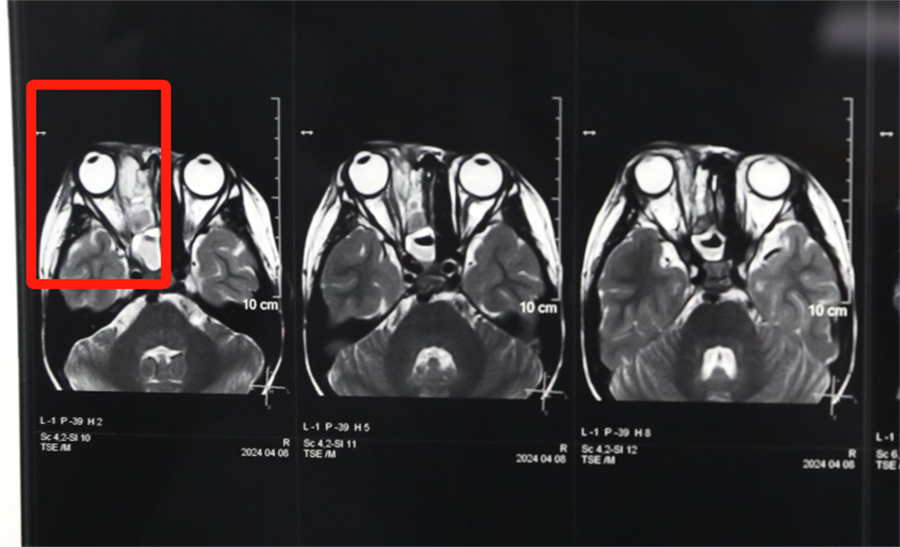

经眼科、耳鼻喉科联合会诊,医生发现孩子是因为患了急性鼻窦炎,导致右眼急性细菌感染,确诊为“右侧眶蜂窝织炎、眶内脓肿”。考虑到此病进展较快,可能导致视力下降甚至失明,耳鼻喉科立即将患儿收治入院。静脉输液、对症支持治疗、密切监测视力变化,一切有条不紊。入院第2天,孩子自觉右眼视力下降明显,眼科紧急会诊发现,其右眼视力从患病前的1.0下降到0.4。

北京儿童医院常驻专家、a片网站 副院长杨小健决定立即手术治疗引流眶内脓液,并组织多学科联合会诊。考虑到患儿年龄较小,杨小健副院长决定采取内镜经鼻腔手术引流脓液,这种手术方式创伤小、恢复快、效果确切,而且避免了外切口瘢痕,不需要反复进行局部消毒换药。但是孩子鼻腔解剖结构本身就狭窄,而且处于急性感染期,术中出血风险较大,手术难度较高,对麻醉技术也有着很高的要求。

最终,杨小健副院长熟练地将手术器械通过小小的鼻孔,伸入到曾被公认为“手术禁区”的眶鼻交界区。一个多小时后,她成功地将眼眶脓肿充分引流出来。术后,医院多学科团队密切观察患儿病情变化,每日查房讨论并及时调整治疗方案。最终,通过全体医护人员的共同努力,患儿术后第3天右眼斜视就消失了,视力也恢复到了1.0。术后5天,患儿高高兴兴地出院了。